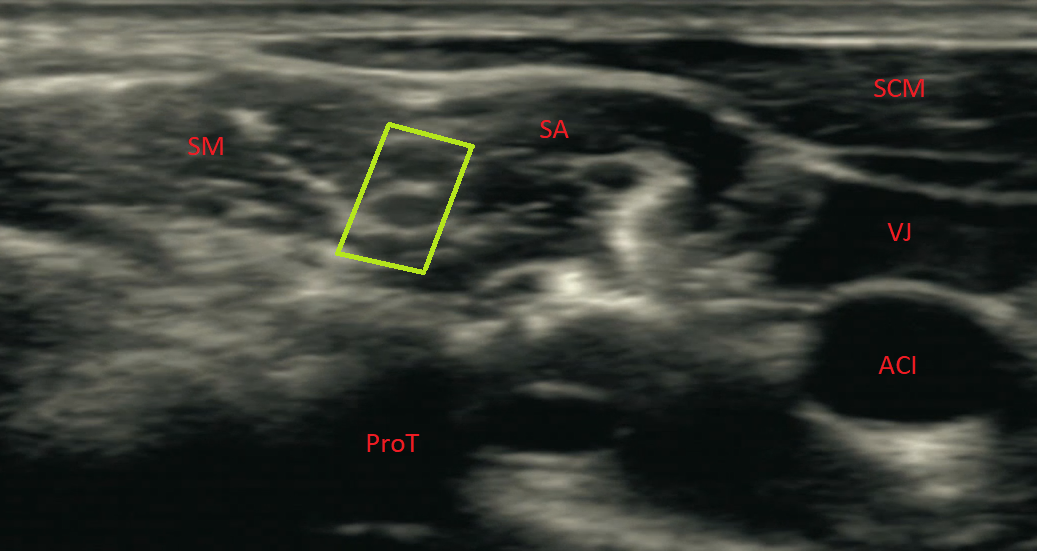

Sonoanatomie

Sonographisch sollte der Schallkopf im mittleren Drittel der Clavicula aufgesetzt werden, führt man den Schallkopf nun nach kranial, erscheint im Schallfenster bei Kippen des Schallkopfes nach thorakal die Arteria subclavia, die der Pleura aufliegt. Lateral der Arterie lässt sich der Plexus brachialis in supraclaviculärer Position darstellen. Ist dieser sicher identifiziert, so kann er durch Kippen des Schallkopfes und sanftes Vorrutschen nach kranial bis in die interskalenäre Position verfolgt werden. In der Tiefe zeigt sich meist ein Knochenschatten, der dem Processus transversus C7 entspricht. Medial an der Oberfläche zeigen sich laterale Anteile des Sternocleidomastoideus, darunter gelegen der schmale Musculus scalenus anterior und weiter lateral der meist etwas prominentere Musculus scalenus medius. Die beiden Scalenusmuskeln bilden die Scalenuslücke und werden von einer Faszie bedeckt, die nicht zwingend visualisiert, jedoch bei der Out-of-Plane-Technik zwingend durchstochen werden muss. Am Oberrand der Scalenuslücke lassen sich jetzt die Nervenfasern von C5, darunter die meist zweigeteilten Fasern von C6 und in der Tiefe, in Nähe zum Processus transversus, die prominenten C7 Fasern darstellen. Medial der C7 Faser findet man manchmal die Arteria und Vena vertebralis.

CAVE: Es gibt beim interskalenären Plexus brachialis häufig anatomische Variationen. Die Nervenfasern von C5 können durchaus im M. scalenus medius oder außerhalb der Scalenuslücke verlaufen.

- Grünes Rechteck: Plexus brachialis in der vorderen Scalenuslücke, von vorne nach hinten C5, C6 und C7

- ACI: A. carotis interna

- VJ: V. jugularis interna

- SCM: M. sternocleidomastoideus

- SA: M. scalenus anterior

- SM: M. scalenus medius

- ProT: Processus transversus von einem Halswirbelkörper